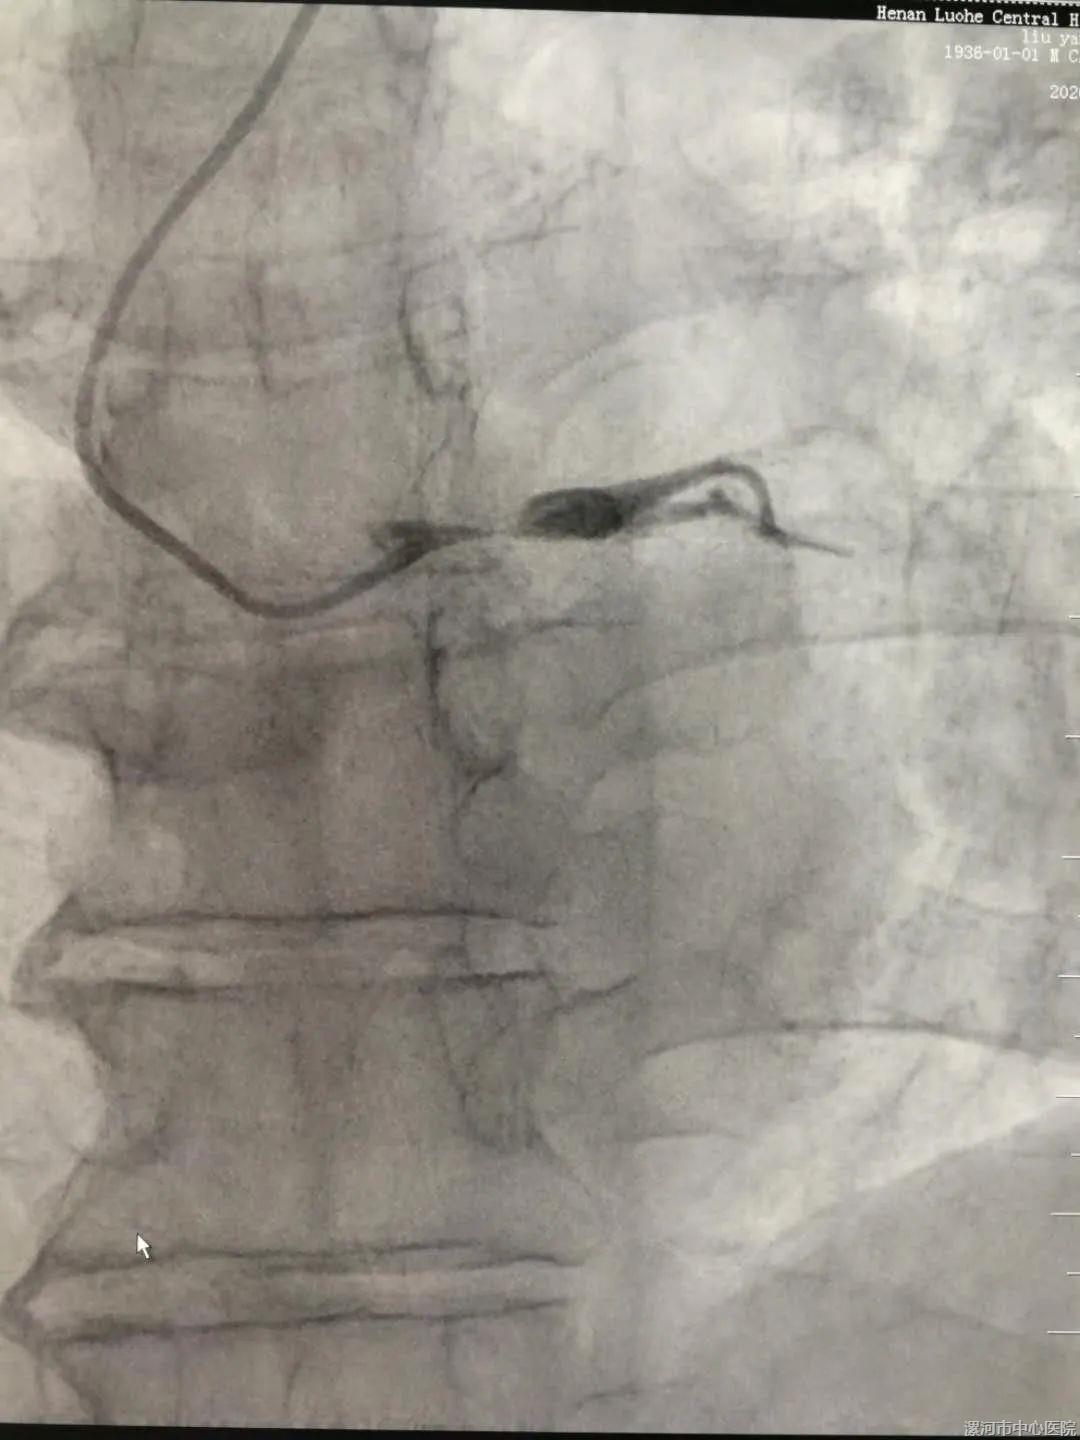

① 术前

13点25分,患者进行穿刺并行冠脉造影,明确诊断为“急性心肌梗死 左主干急性闭塞”,立即与老先生家属进行充分沟通后,取得老先生家属的充分理解及同意。

14点1分,在刘东亮教授的精心指导下,全体手术医师、技师、护士通力配合,导丝顺利通过左主干闭塞处,成功开通急性闭塞的血管,于左主干植入1枚支架,行血管内超声检查提示左主干支架贴壁膨胀良好。经过积极的抢救,老先生的心率、血压平稳下来了,冠状动脉内血流逐渐恢复正常,生命体征趋于稳定,随即返回CCU病房密切监护治疗。